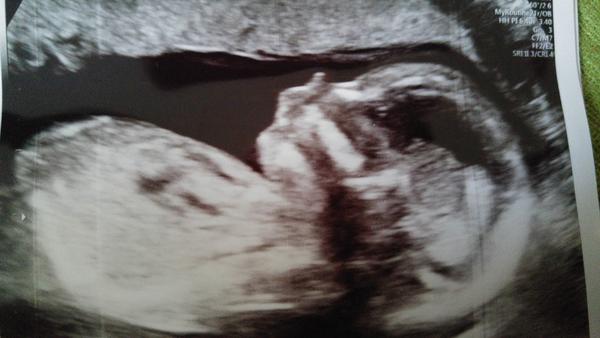

Tak babulky, 3D ultrazvuk za nami, bol tam aj moj muz aj moj syn. Videli sme pipika tak jasne, ze to uz jasnejsie ani byt nemohlo, ako povedal pan doktor. Tak moji chlapi sa velmi tesia - starsi je hrdy ze vie robit synov, mladsi sa tesi ze nebude mat v izbicke babiky 😅

Vyzera to ,ze troch dievcatach budeme mat chlapceka🤗😆🤗

Tak babulky budeme mať chlapčeka. Tešila som sa na dievčatko, ale čo už. Hlavne nech sme zdravučky.